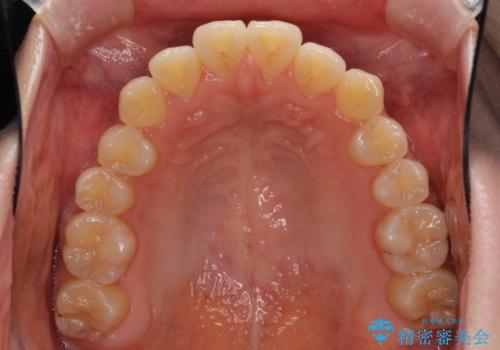

オープンバイトのインビザラインを用いた再矯正

- 矯正治療の後戻りを気にして来院された患者様です。

オープンバイト(前歯の開咬)と下顎骨の偏位による不正咬合が認められました。

骨格の偏位による不正咬合は改善しきれないことを理解いただいた上で、インビザラインにて矯正治療を行うこととしました。

オープンバイトは後戻りを起こしやすいため、極力そのリスクを軽減するため、奥歯を圧下させるように治療を進めていきました。

下顎骨の偏位が顕著であったため、上下の正中を合わせることはできませんでしたが、患者様には大変満足していただきました。